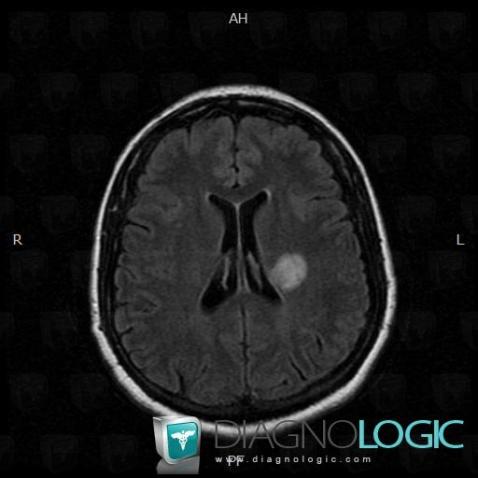

Multiple sclerosis, Cerebral hemispheres, MRI

Here is the specific information in the key image above:

- Diagnosis Multiple sclerosis, Location(s) Cerebral hemispheres, with gamuts Intracerebral T2W or FLAIR hyperintense lesion, White matter disease